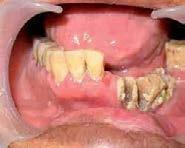

Imagen 8. Osteorradionecrosis de los maxilares Imagen 7. Osteorradionecrosis de los maxilares.

La etapa previa a la radioterapia es el momento ideal para poder determinar qué dientes pueden ser restaurados y cuáles no, con la finalidad de realizar las exodoncias necesarias así como cirugía oral, con al menos 3 semanas de anticipación para lograr una adecuada cicatrización. Se deben realizar los tratamientos odontológicos que requiera el paciente, tales como, eliminación de caries, eliminación de sarro dental y posibles bolsas periodontales, eliminar cualquier prótesis, dentadura o borde filoso que pueda ocasionar irritaciones o lesiones en la mucosa. Es muy importante enfatizarle al paciente que debe cumplir con una higiene oral escrupulosa, así como acudir a revisiones frecuentes para aplicación tópica de flúor.

La situación cambia radicalmente en las etapas de irradiación y postradiación. Como ya se ha mencionado, el tejido óseo irradiado es “3 H”, hipocelular, hipovascular e hipóxico, por lo que al no tener capacidad de regeneración, las exodoncias y cualquier otro procedimiento que implique trauma a estos tejidos, deben evitarse hasta por un periodo de 10 años posteriores a la radioterapia (Imagen 7 y 8).